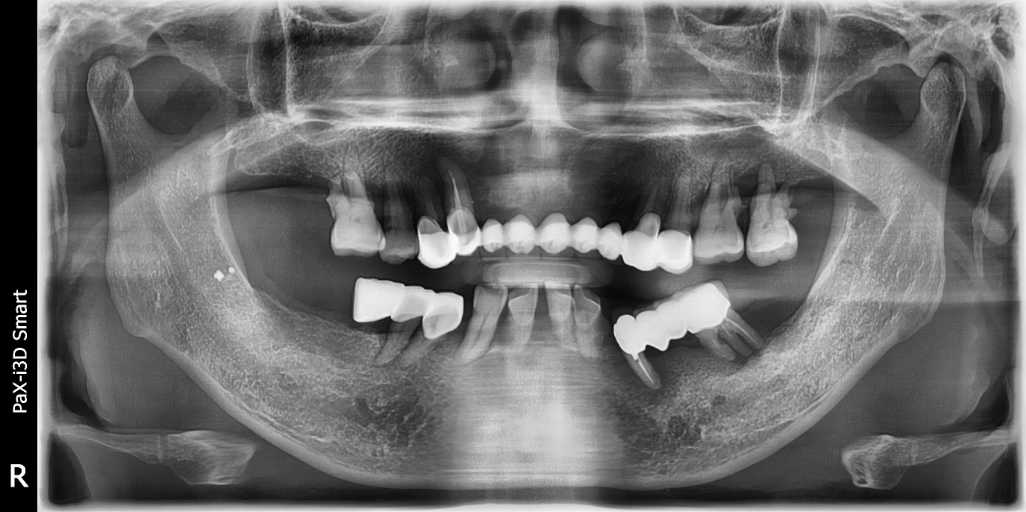

#무치악 임플란트 환자 사례 : 기존 치아의 염증 상태로 인해 치료 시작일 때, 잔존치 전체 발치 + 상악동거상술(양쪽) + 뼈이식다수 + 임플란트 픽스처(뿌리) 17개 식립